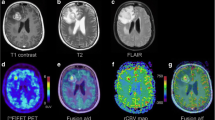

In PD median values for TBRmean (2.23 vs. 0.97, p < 0.001), TBRmax (2.28 vs. 1.04, p < 0.001) and rCBVmean (1.78 vs. 1.18, p < 0.001) were significantly higher and those for rTTP (1.01 vs. 1.11, p < 0.001) significantly lower than in RN (Table 2). While median values for rCBFmean (1.48 vs. 0.8, p = 0.098) and rMTT (1.1 vs. 1.04, p = 0.801) differed between PD and RN, the difference was not statistically significant. In single parameter analysis, rTBRmean (AUC = 0.91, p < 0.001), rTBRmax (AUC = 0.89, p < 0.001), rTTP (AUC = 0.87, p < 0.001) and rCBVmean (AUC = 0.84, p < 0.001) were efficacious for discrimination of PD from RN (Figs. 1, 2 and 3). rCBFmean (AUC = 0.68, p = 0.09) and rMTT (AUC = 0.47, p = 0.51) did not reach statistical significance. According to Pearson’s correlation coefficient, TBRmean and TBRmax were highly correlated with each other. Due to the correlation and the higher AUC of the former parameter, TBRmax was excluded for further analysis. Optimal cut-offs, sensitivities, specificities, and accuracies for discrimination of PD from RN are given in Table 2.

ROC curves for PWI-MRI and [18F]FET-PET parameters ROC curves and their respective AUC values for PWI-MRI (rCBVmean, rCBVmean, rMTT, rTTP) and [18F]FET-PET (TBRmean, TBRmax) parameters for differentiation between progressive disease and radiation necrosis. TBRmean yielded the highest AUC, followed by TBRmax, rTPP, rCBVmean, rCBFmean and rMTT. ROC receiver operating characteristic, PWI-MRI perfusion weighted magnetic resonance imaging, [18F]FET-PET O-(2-[18F]fluoroethyl-)-l-tyrosine-positron emission tomography, rCBVmean mean relative cerebral blood volume, rCBFmean mean relative cerebral blood flow, rMTT relative mean transit time, rTTP relative time to peak, TBRmean mean tumor to brain ratio, TBRmax maximal tumor to brain ratio, AUC area under the curve

Progressive disease example of a patient with tumor progression, 7 months after initial diagnosis of anaplastic astrocytoma, resection and chemoradiotherapy the patient clinically deteriorated. Axial T1-weighted contrast-enhanced MRI (a) demonstrates right hemispheric progressive tumor tissue, corresponding PWI maps CBV (b), CBF (c), MTT (d), TTP (e) and [18F]FET-PET (f) imaging are depicted. MRI magnetic resonance imaging, PWI perfusion weighted imaging, [18F]FET-PET O-(2-[18F]fluoroethyl-)-l-tyrosine-positron emission tomography, CBVmean mean cerebral blood volume, CBFmean mean cerebral blood flow, MTT mean transit time, TTP time to peak, TBRmean mean tumor to brain ratio, TBRmax maximal tumor to brain ratio

Radiation necrosis example of a patient with radiation necrosis 20 months after initial diagnosis of glioblastoma, resection and chemoradiotherapy, follow-up imaging showed a new contrast enhancing lesion. Axial T1-weighted contrast-enhanced MRI (a) demonstrates right hemispheric necrosis, corresponding PWI maps CBV (b), CBF (c), MTT (d), TTP (e) and [18F]FET-PET (f) imaging are depicted. MRI magnetic resonance imaging, PWI perfusion weighted imaging, [18F]FET-PET O-(2-[18F]fluoroethyl-)-l-tyrosine-positron emission tomography, CBVmean mean cerebral blood volume, CBFmean mean cerebral blood flow, MTT mean transit time, TTP time to peak, TBRmean mean tumor to brain ratio, TBRmax maximal tumor to brain ratio